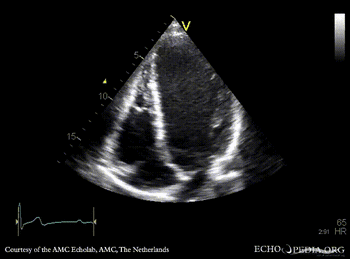

E00231.gif E00232.gif

PLAX: prolapse of aortic valve PLAX: Color Doppler severe aortic regurgitation, eccentric jet